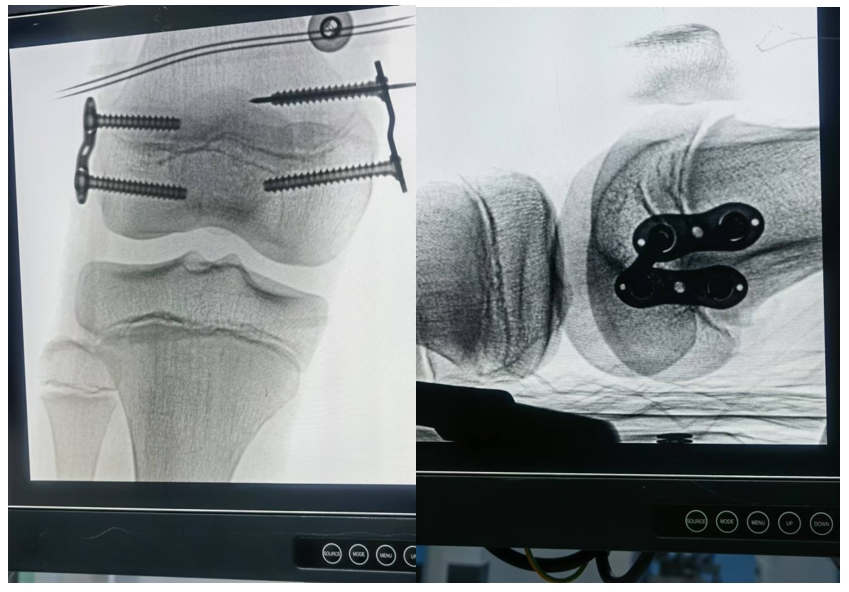

我院骨病诊疗中心李刚博士,采用数字骨科技术通过医工结合的方式,为儿童股骨远端内外侧骨骺固定术患者,依据患者磁共振数据进行高精度的三维图像构建,精准的术前规划、个性化穿针固定导板设计,为10例患者成功实施微创手术治疗,取得了满意效果。

核磁共振可避免射线对儿童健康的影响,且MR图像能清晰显示股骨远端内外侧骨骺的解剖结构、病变范围及周围软组织情况,但三维成像难度较大。医工结合团队多次讨论,共同参与设计三维图像结构,并模拟手术治疗固定点的位置、角度和深度等,并根据三维成像设计个性化手术固定导板,利用3D打印技术个性定制,术中精准引导手术操作,使手术过程更加高效。术中,通过小切口进行微创精准操作,相比传统开放手术,减少了对周围组织的损伤,减少了手术时间和术中出血,避免了神经血管损伤风险,降低了术后感染、瘢痕形成等并发症。